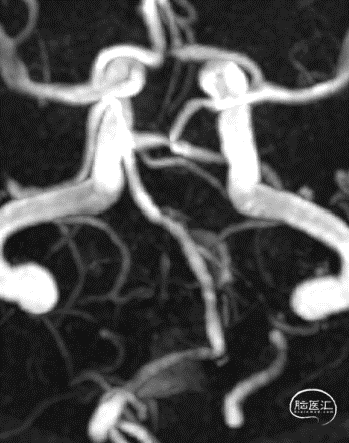

入院时头颅MRA

院前MRI

术后3个月MRA

术后3个月MRA复查提示:支架内血流通畅,动脉瘤体积进一步缩小。准备6-12月期间复查脑血管造影